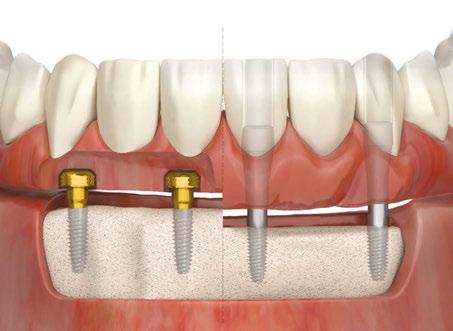

The treatment of edentulous arches with full-arch fixed dental prosthetics is the oldest form of restorations placed on root form endosseous implants as presented by Brånemark, et al., in 1977.1 Many different tech niques and philosophies of fixed full-arch restorations have been developed and described in the past 55 years, which include, but are not limited to, different types of restorative materials, implant numbers and angulations, management of the restorative space, healing protocols, and analog or digital workflows. Even though some of these variations of full-arch therapy may be clinically simpler to perform than others, the final prostheses usually require final insertion with prosthetic screws that make the prosthetic material easier to fracture and create the necessity to utilize materials to seal screw access holes. These issues increase the maintenance times and the potential for prosthetic complications throughout the life of the prostheses.

Imagine being able to design and build an FP-3 fullarch (fixed-detachable hybrid) prosthesis, utilizing the current techniques used to make a simple denture or overdenture. Imagine being able to deliver these pros theses with a single snap and perform maintenance and repair appointments without having to drill screw access covers, removing screws, choosing new screws, torqu ing the prosthesis, and resealing it after the required procedure.

known removable overdenture abutment (Zest LOCATOR®), with a new FDA-approved fixed prosthetic attachment (LOCA TOR FIXED™ Attachment System), while using traditional den ture fabrication procedures.

For over 4 decades, the delivery of full-arch implant pros thetics has been a convoluted series of clinical and laboratory procedures that have made it challenging for the general prac titioner to make this therapy easily accessible to a great num ber of patients in need. The use of the traditional LOCATOR abutment with the LOCATOR FIXED Attachment System and

simple removable prosthetic techniques will make full-arch implant rehabilitation a more predictable and economical way to reach many underserved patients. It will allow more general dentists to grow personally and professionally. And it will make the hygiene, maintenance, and repair appointments simpler and more efficient for the general dental practice.